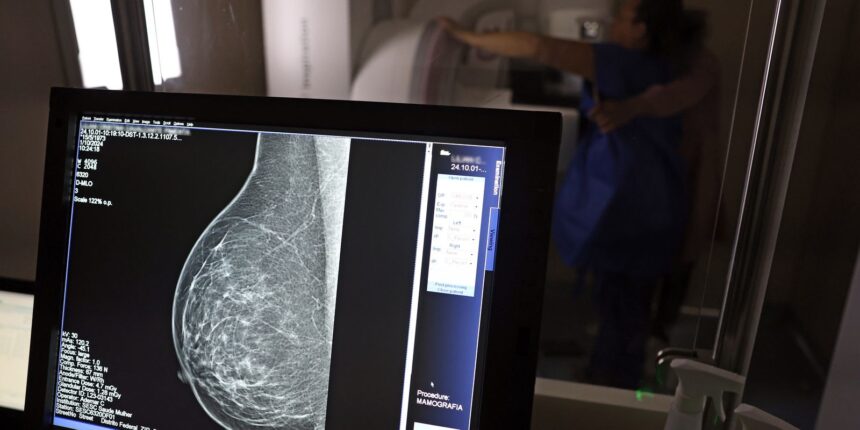

Dados do Painel Oncologia Brasil, analisados pelo Colégio Brasileiro de Radiologia e Diagnóstico por Imagem (CBR), indicam que mais de 108 mil mulheres com menos de 50 anos foram diagnosticadas com câncer de mama no Brasil no período entre 2018 e 2023 – uma média de uma em três mulheres diagnosticadas com a doença.

Para a entidade, os números reforçam a importância de ampliar o rastreamento do câncer de mama por meio da realização de mamografia em mulheres abaixo dos 50 anos e acima dos 70 anos, faixas etárias que não estão incluídas na recomendação padrão de exames preventivos no âmbito do Sistema Único de Saúde (SUS).

O levantamento mostra que, entre janeiro de 2018 e dezembro de 2023, o Brasil registrou mais de 319 mil diagnósticos de câncer de mama, sendo 157,4 mil em mulheres de 50 a 69 anos, faixa etária atualmente recomendada para o rastreamento.

Entre mulheres com idade entre 40 e 49 anos, foram registrados 71.204 casos de câncer de mama, enquanto 19.576 mulheres com idade entre 35 e 39 anos também receberam o diagnóstico da doença. Juntas, ambas as ocorrências representam 33% do total de casos diagnosticados no período.

Já entre mulheres acima de 70 anos, foram identificados 53.240 casos de câncer de mama.